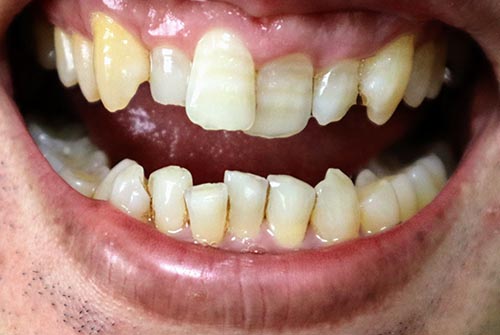

歯の並びが悪い方の特徴

歯の並びが悪い方の特徴としては、汚れが溜まりやすいことです。

歯並びが良い方であっても、歯の形は海岸のように凸凹しています。皆さんも、ご自分の歯を触ってみると良くわかると思いますが、平らではありません。プラスして歯並びが悪い方は、汚れが溜まりやすいので、通常の方が3ヶ月に1度のクリーニングで良くても、2ヶ月に1度くらいのクリーニングと日々の歯ブラシは、1日4回くらいで時間も長めの10分くらいがおすすめになります。

つまり、歯並びが悪いとリスクが上がりますので、要注意が必要になりますので、歯科医院でのクリーニングはもちろんですが、自宅での日々のブラッシングはもっともっと重要になります。

おすすめのクリーニングは、歯と歯の間を中心に汚れを除去してもらい、やはりキレイにフロッシングで、普段届かない汚れも除去してからのフッ素コーティングがベストになります。歯の表面のクリーニングももちろん重要ですが、歯と歯の間のクリーニングを中心に行うのがおすすめになります。